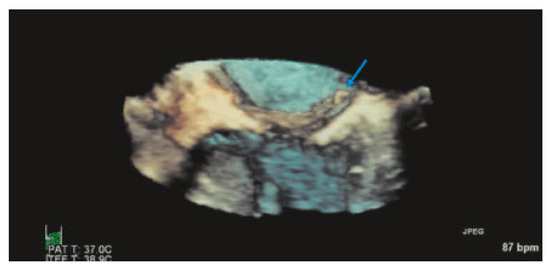

Value of Echocardiography in Differentiation of Acute Dyspnoea

by Ioannis Kapos and Felix C. Tanner

Echocardiography is one of the most effective imaging modalities for investigation of patients with acute dyspnoea. This review summarises appropriateness criteria and current guidelines for the use of cardiac ultrasound in common clinical scenarios presenting with acute dyspnoea, and illustrates such scenarios with [...] Read more.

Echocardiography is one of the most effective imaging modalities for investigation of patients with acute dyspnoea. This review summarises appropriateness criteria and current guidelines for the use of cardiac ultrasound in common clinical scenarios presenting with acute dyspnoea, and illustrates such scenarios with typical echocardiographic findings. Full article

Show Figures

Figure 1